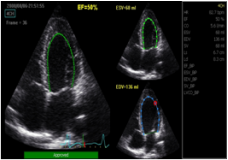

1.自动心功能测量(2DAutoEF)

基于目前最前沿的心肌斑点追踪技术而发展的临床诊断工具,VividE95自动追踪心内膜边界,从而计算出舒张期和收缩期左心室容积变化,计算SV、CO、EF等评价心功能的参数。通过分析和追踪自动显示心内膜边界的变化,可减少我们对心内膜识别的主观依赖,为临床提供了更准确的分析数据,比M型测量更快捷的工作流程。